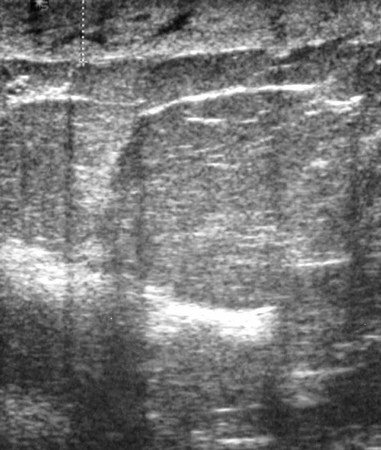

Simple cysts are completely anechoic, are distinct from the surrounding breast tissue on breast ultrasound, and are benign.[18][Figure caption and citation for the preceding image starts]: Ultrasonographic image of a simple cystCourtesy of Dr Lane Roland, University of Louisville; used with permission [Citation ends].

Complex cysts are associated with internal septations or debris, and should raise the suspicion of malignancy. National Comprehensive Cancer Network (NCCN) guidance recommends core needle biopsy of complex cysts.[19][Figure caption and citation for the preceding image starts]: Ultrasonographic image of a complex cystCourtesy of Dr Lane Roland, University of Louisville; used with permission [Citation ends].